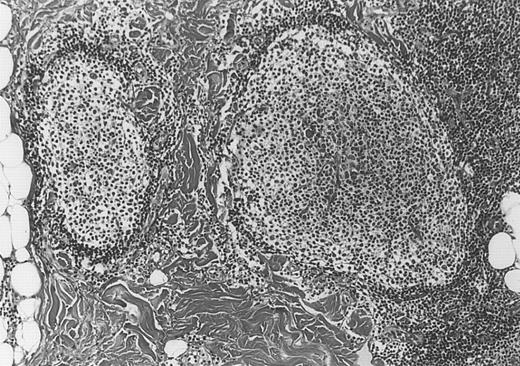

Neoplastic follicles.

The follicles lack a normal mantle zone and reveal nearly complete absence of tingible body macrophages (patient 9).

All cases of follicular lymphoma were classified as grade 2 according to the REAL classification. Histology showed bottom-heavy lymphoid infiltrates with prominent follicular pattern (Figures3 and 4). A well-formed mantle zone around most follicles was present only in 2 patients. In the other specimens the mantle zone was either reduced (11 patients) or nearly absent (2 patients) (Figure5). A clear-cut marginal zone was never observed. Tingible body macrophages within follicles were present only in 1 patient and were absent in the other 14 patients. Cytomorphology of follicles in all patients showed variable proportions of centrocytes (cleaved follicle center cells) and centroblasts (Figure6). The interfollicular areas revealed the presence of small lymphocytes and histiocytes admixed with a few larger cells and occasionally other inflammatory cells such as eosinophils and plasma cells.